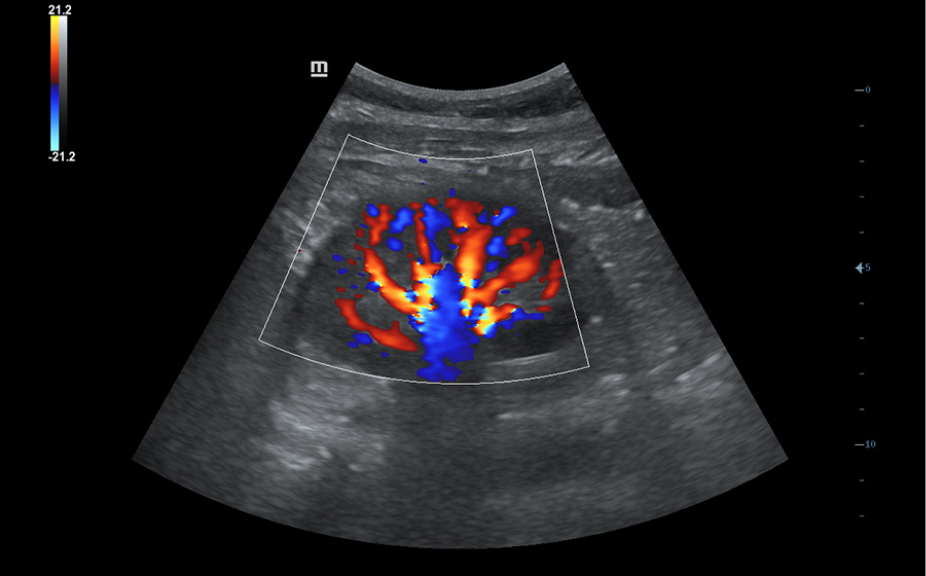

?ematik ve ultrason resimleri dahil, normal anatomik g?sterimler.

Standart ultrasonogram?n, ilgilenilen b?lge ĂŒzerinde g?rsel rehberlik sa?layan yan

g?rĂŒnĂŒmĂŒ.

Standart ultrason g?rĂŒntĂŒleri

3

Referans i?in ger?ek zamanl? tarama kar??la?t?rmas?.